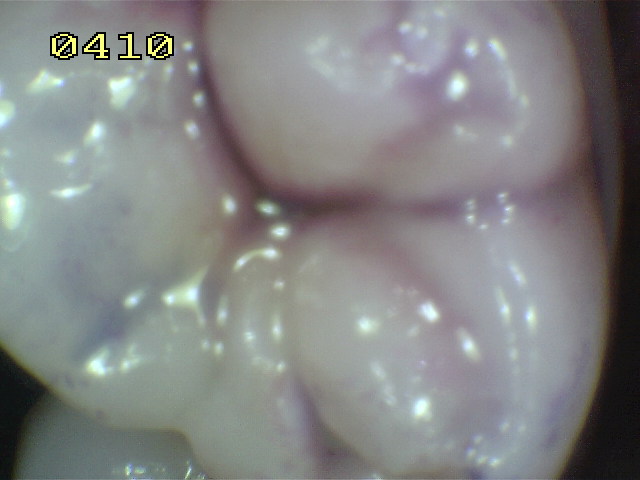

Este índice es utilizado para evaluar la higiene de las caras oclusales. Para ello se utiliza una solución reveladora de placa bacteriana (doble tono). El paciente debe realizar un buche con agua para eliminar el exceso de colorante. En el siguiente cuadro se observa los criterios utilizados:

Índice de placa oclusal

0

No hay placa.

1

Placa de color rosa en surco.

2

Placa de color rosa en surco con islotes azules.

3

Placa de color azul en surco.

Criterio preventivo según resultados del índice placa oclusal:

Continuar con la higiene que realiza el paciente.

Realizar  barniz fluorado ó barniz con clorhexidina en dientes temporarios

Realizar selladores de fosas y fisuras en dientes permanentes

Las cerdas del cepillado dental no llegan a barrer la placa bacteriana del fondo del surco. Para la eficacia óptima, los selladores deben estar presentes en todos los puntos y fisuras. La condición del seallador  debe observarse regularmente durante las visitas de control dental y si es requerido deberá  ressellar o repararlo. (237)